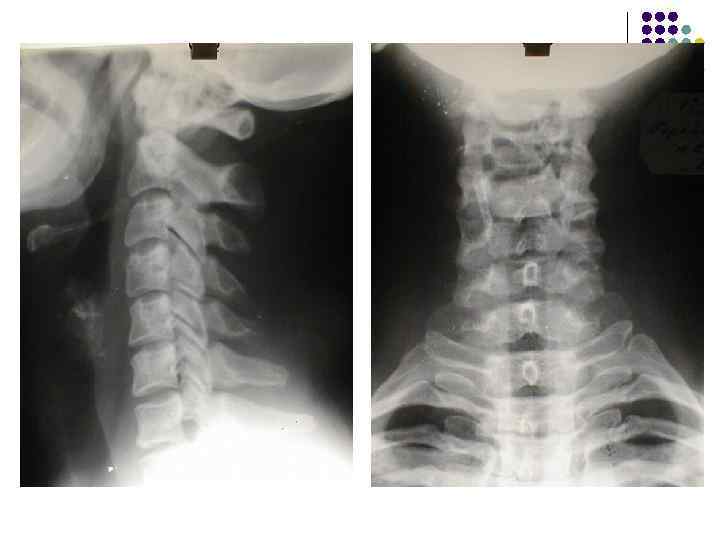

l l l На рентгенограмме шейного отдела позвоночного столба в боковой проекции определяется: выраженные распространенные дистрофические изменения в виде остеохондроза и артроза дугоотростчатых суставов: неравномерное сужение межпозвонковых пространств, субхондральный остеосклероз, костные разрастания по краям тел позвонков, сужение рентгеновских суставных щелей дугоотостчатых суставов с субхондральным остеосклерозом и небольшими костными разрастаниями по краям суставных поверхностей. Наиболее ярко эти изменения выражены в сегментах С 5 -6 -7 Признаки ограниченного смещения тел позвонков в виде симптома «распорки» и кифотической установки. Заключение: Остеохондроз шейного отдела позвоночного столба. Артроз дугоотростчатых суставов. Деформация шейного отдела позвоночника с нарушением статики.

1.

l l l На рентгенограмме шейного отдела позвоночного столба в боковой проекции определяется: выраженные дистрофические изменения за счет остеохондроза - значительное, неравномерное сужение межпозвонковых пространств с нарушением их правильной клиновидной формы, выраженный субхондральный остеосклероз, значительные костные разрастания по передним краям тел позвонков. Наиболее ярко эти изменения представлены в сегментах С-5, 6, 7. Помимо этого, в этих же сегментах фиксируются дистрофические изменения дугоотростчатых суставов – сужение рентгеновских суставных щелей, субхондральный остеосклероз и костные разрастания по краям суставных поверхностей. Выпрямление физиологического лордоза. Признаки системного нарушения статики тел позвонков в виде симптомов кифотической установки. Деструктивных изменений нет Заключение: Комплекс дистрофических изменений шейного отдела позвоночного столба в виде остеохондроза и артроза дугоотростчатых суставов с преимущественными проявлениями в нижних сегментах отдела. Нарушение статики тел позвонков

3.

l На рентгенограмме шейного отдела позвоночного столба в боковой проекции определяется: выраженные дистрофические изменения за счет остеохондроза с преимущественными проявлениями в сегменте С 5 -6 – сужение и деформация межпозвонковых пространств, выраженный субхондральный остеосклероз, значительные костные разрастания по краям тел позвонков. Выпрямление физиологического лордоза. Признаки нарушения положения тела С 4 (симптом «распорки» )

l На рентгенограммах шейного отдела позвоночного столба в двух проекциях определяется комплекс выраженных дистрофических изменений с преимущественными проявлениями в сегментах С 5 -6 -7 в виде остеохондроза и выраженного спондилоза за счет неравномерного сужения межпозвонковых пространств, субхондрального отсеосклероза и костных разрастаний как по краям тел позвонков с продолжением плоскости замыкательной площадки, так и под передней продольной связкой с образованием мощного костного соединения. Положение тел позвонков правильное, деструктивных изменений нет.